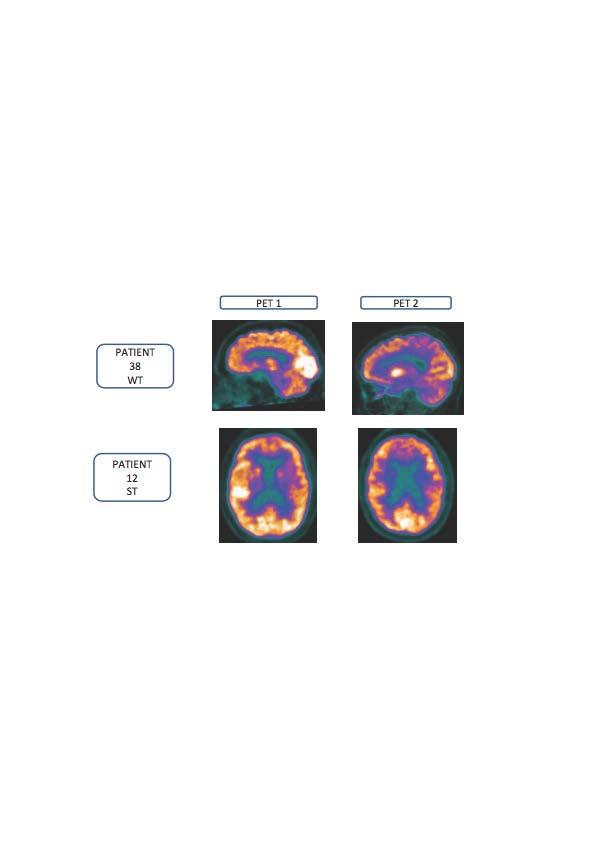

image: 18F-FGD-PET scans of two patients, without nutritional intervention (top row) and with nutritional intervention with the drink containing Fortasyn Connect® (bottom row) at the beginning and after eight months of intervention.

Neuropsychological tests and 18F-FDG-PET imaging were conducted at the inclusion visit and checked again at the one-year follow-up, which also included a neurological examination and a Subjective Changing Scale completed by the caregiver. Seventeen patients received the product while 24 patients were in the group without intervention, and two patients withdrew.

F-FDG-PET imaging studies provide a measure of the number of synapses in a brain region (this number decreases in mild cognitive impairment progressing to more advanced AD); the ability of this food for special medical purposes to impact this decrease in synaptic number was assessed.

18F-FDG PET scans showed a significant worsening in the group without nutritional intervention compared with the group receiving the product. There was a significant worsening in memory performance, executive functions and attention in the group without intervention, while the group receiving the product showed a stabilization in these outcome measures. Similarly, caregivers indicated a stabilization/improvement in the group with nutritional intervention. This observational real-life study illustrates the positive experience of clinical use of this food for special medical purposes.

Richard Wurtman, MD, who developed the multinutrient combination Fortasyn Connect® with colleagues at the Massachusetts Institute of Technology Department of Brain and Cognitive Sciences, Cambridge, MA, USA, explained, "Most people had thought any effective intervention would involve getting rid of brain amyloid-beta, a presumed toxin that was believed to destroy brain synapses. This study by Dr. Manzano and colleagues shows that this nutritional intervention works in patients by an entirely different biochemical mechanism. Rather than blocking a neurotoxin's effect, the data suggest that by providing nutritional support, it can help brain neurons make more synapses. This hypothesis is supported by the new data on 18F-FDG PET that there was significant worsening in the individuals who had not received the nutritional intervention and less worsening among those receiving the intervention. That is, as they say, a 'big deal.'"